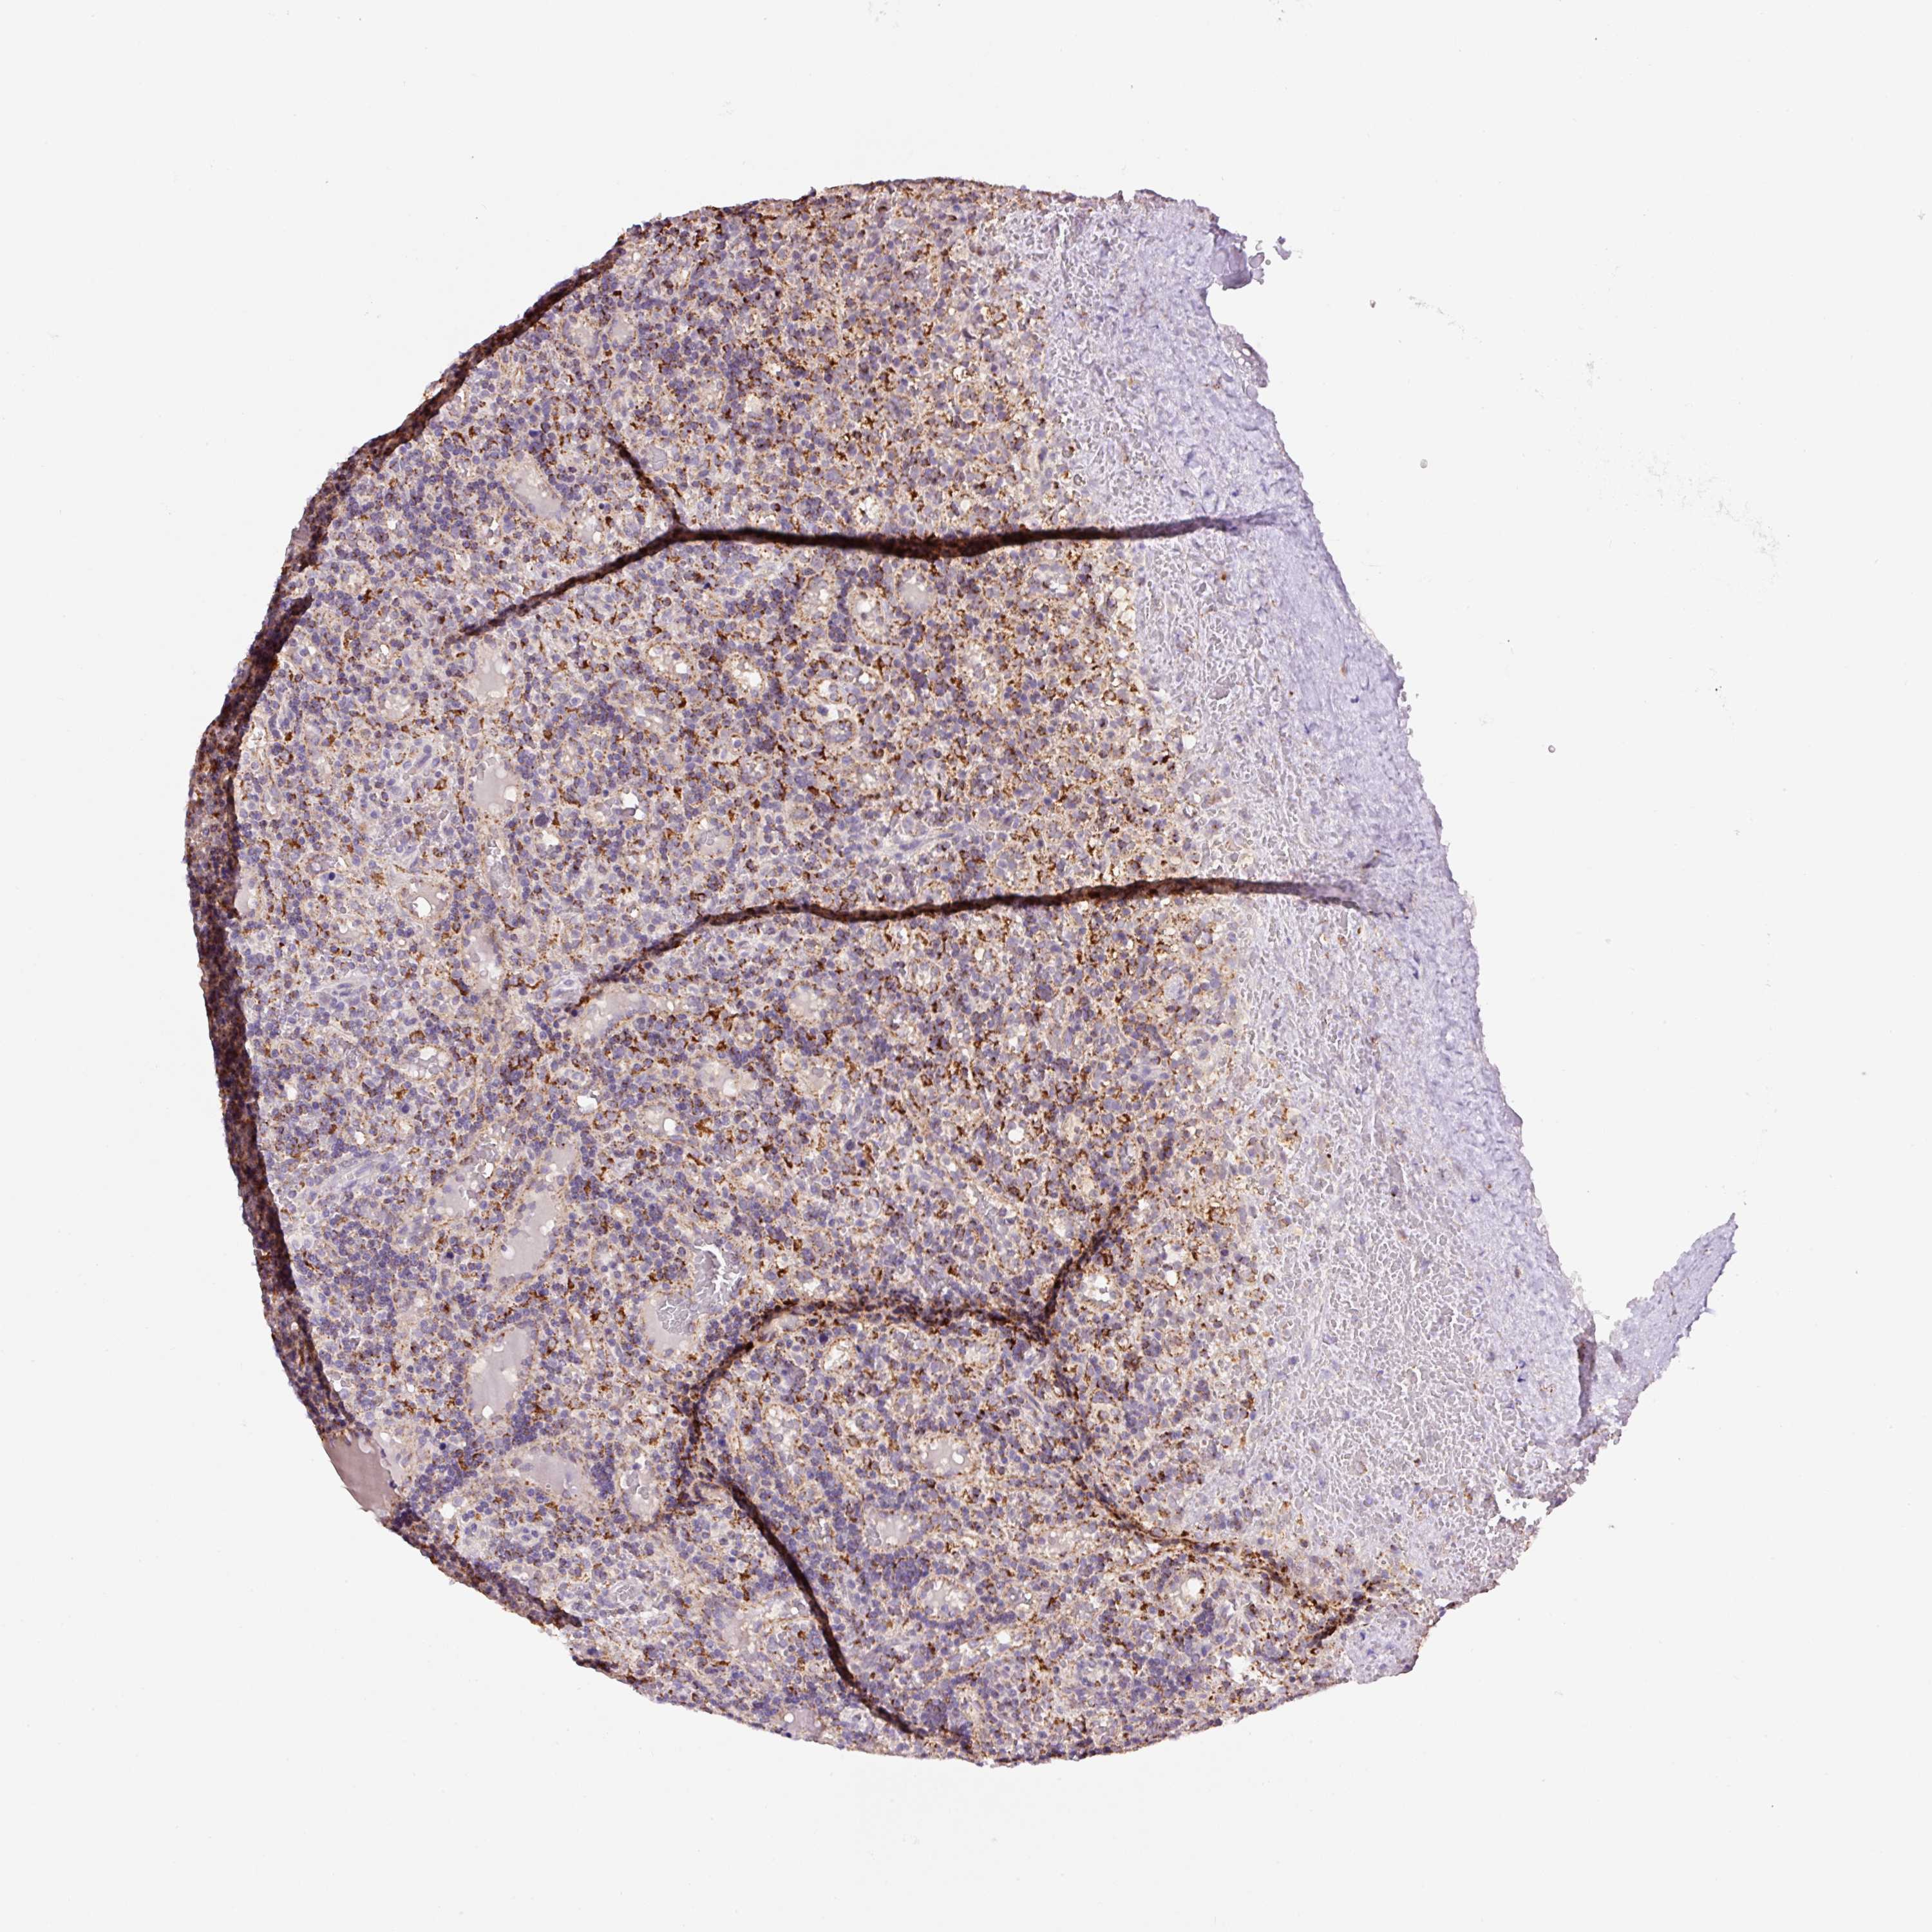

CANCER LYMPHOMA Show tissue menu

LYMPHOMA - Protein expressioni

A mouse-over function shows sample information and annotation data. Click on an image to view it in a full screen mode. Samples can be filtered based on level of antibody staining by selecting one or several of the following categories: high, medium, low and not detected. The assay and annotation is described here.

Each image is clickable and will lead to virtual microscopy that enables deeper exploration of all samples and also displays staining intensity scores, fraction scores and subcellular localization as well as patient and tissue information for each sample.

Antibody HPA051162

Antibody HPA053502

Antibody CAB018734

Staining

High

Medium

Low

Not detected

Intensity

Strong

Moderate

Weak

Negative

Quantity

>75%

75%-25%

<25%

None

Location

Nuclear

Cytoplasmic/membranous

Cytoplasmic/membranous,nuclear

Hodgkin's disease, NOS

Malignant lymphoma, non-Hodgkin's type, High grade

Malignant lymphoma, non-Hodgkin's type, Low grade